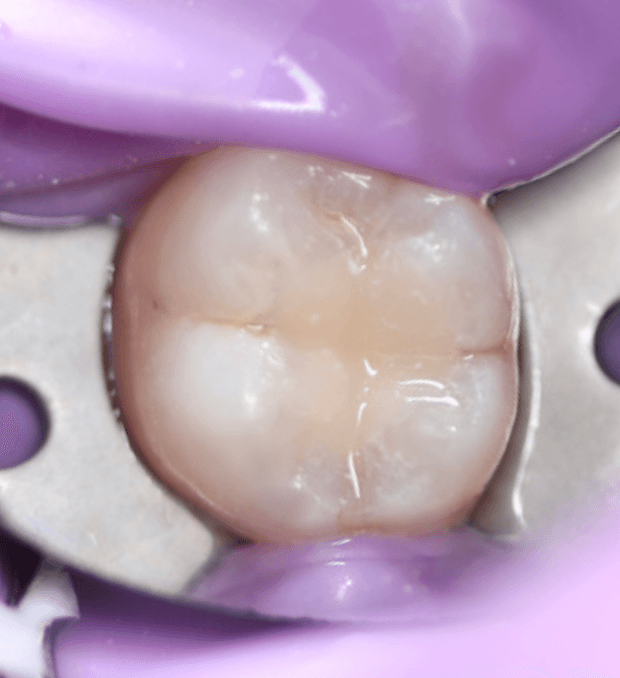

This case involved a direct composite restoration to manage occlusal caries secondary to an existing GIC. Rubber dam isolation provided excellent moisture control and visibility, allowing for precise cavity preparation and layering technique. Upon reviewing the completed restoration in natural light as well as the photographs, a more accurate shade match would’ve been advantageous. The case reinforced the importance of good isolation for predictable bonding and also helped build my confidence in restoring posterior teeth with attention to anatomy and occlusion.

After Photo